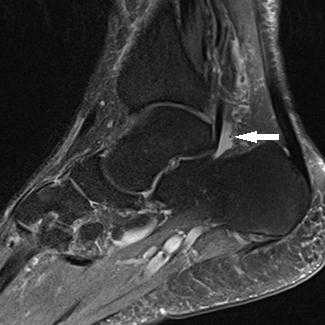

Прежде всего, это боль по задне-внутренней поверхности голеностопного сустава. Возможно «защёлкивание» большого пальца при его сгибании. Хруст, крепитация по задне-внутренней поверхности голеностопного сустава при активных движениях. При физикальном осмотре определяется боль при сгибании большого пальца через сопротивление, при форсированном подошвенном сгибании в голеностопном суставе, при этом боль отсутствует в области первого плюсне-фалангового сустава. Для диагностики повреждения сухожилия длинного сгибателя большого пальца стопы целесообразно выполнение МРТ, при этом обнаруживается скопление жидкости вокруг сухожилия на уровне голеностопного сустава, изменение сигнала от самого сухожилия.